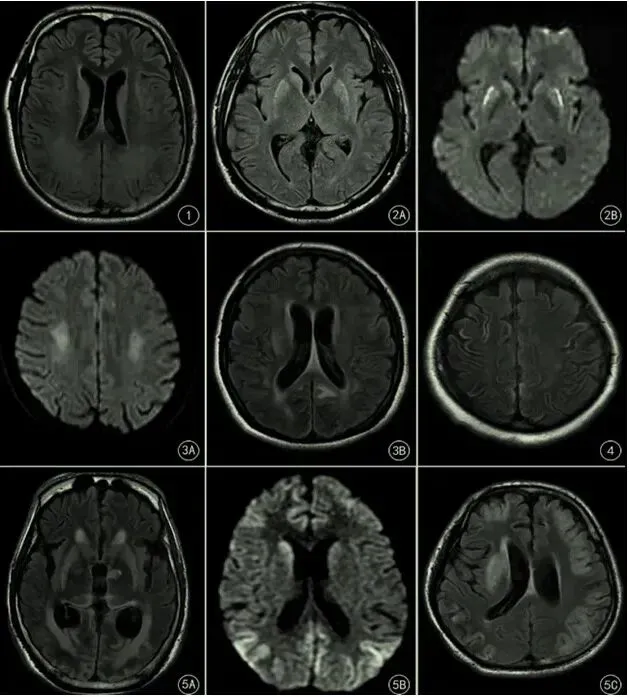

根据其损伤部位分为以下5种类型:

01 脑室周围白质损伤型

脑室周围组织进行性坏死表现为脑室扩大,边缘形态不规则,脑室周围白质损伤以及胼胝体变薄。

02 深部灰质损伤型

包括基底节核团、丘脑、脑干等损伤。

03 分水岭区损伤型

包含两类,分别为皮质分水岭(大脑前动脉-中动脉、大脑中动脉-后动脉交界区的皮质和邻近的皮质下白质),以及内侧分水岭(大脑半卵圆中心及放射冠区的深部白质)。

04 中央沟周围皮质损伤型

05 混合型

包括上述的两种或两种以上的损伤类型。

脑室周围白质损伤型

[1] 男,38岁电击伤致心跳呼吸骤停行心肺复苏成功后,FLAIR示双侧侧脑室旁白质异常高信号。

深部灰质损伤型

[2A,2B] 女,25岁,一氧化碳中毒致心跳呼吸骤停行心肺复苏成功后FLAIR(A)DWI(B)示双侧尾状核和苍白球呈异常高信号。

分水岭型

[3A] 男,40岁,急性脑梗死,突发心脏呼吸骤停行心肺复苏成功后,DWI示大脑半卵圆中心和放射冠区深部白质(内侧分水岭)高信号。

[3B] 女,31岁,宫外孕术中突发心脏呼吸骤停。FLAIR示枕叶(皮层分水岭)斑片状高信号。

中央沟周围皮质损伤型

[4] 女,45岁,剖宫产术后突发心跳呼吸停行心肺复苏成功后,FLAIR示中央沟周围皮质高信号。

混合损伤型

[5A] 男,43岁,无诱因突发心脏呼吸骤停行心肺复苏成功后,FLAIR示双侧基底节、双侧丘脑、双侧后皮层分水岭高信号。

[5B] 女,45岁,剖宫术后心跳呼吸骤停经心肺复苏术后,DWI示双侧尾状核、分水岭高信号。

[5C] 男,25岁,药物中毒导致呼吸衰竭引起心跳呼吸骤停,FLAIR示双多基底节区、大脑皮质高信号。